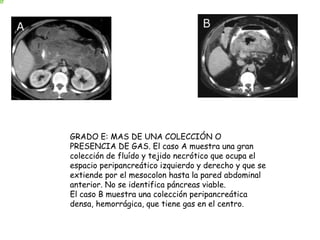

GRADO E: MAS DE UNA COLECCIÓN O

PRESENCIA DE GAS. El caso A muestra una gran

colección de fluído y tejido necrótico que ocupa el

espacio peripancreático izquierdo y derecho y que se

extiende por el mesocolon hasta la pared abdominal

anterior. No se identifica páncreas viable.

El caso B muestra una colección peripancreática

densa, hemorrágica, que tiene gas en el centro.